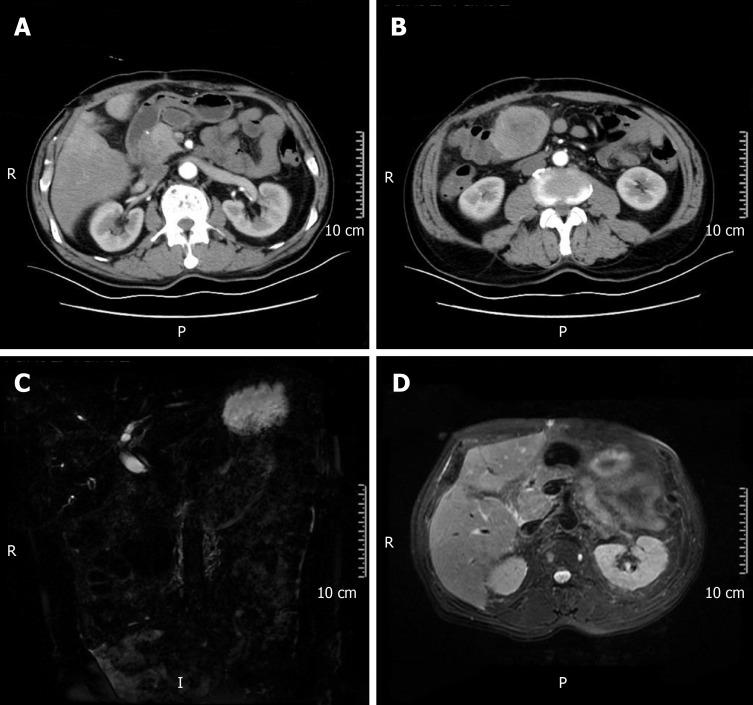

A 64-year-old man was admitted for progressively poor abdominal distension and pain. Liver computed tomography (CT) showed infiltration of gallbladder carcinoma into the adjacent liver, and enlarged retroperitoneal lymph nodes. The patient underwent radical cholecystectomy. Part of the mass was grey and soft, and the neoplastic section showed a purulent-necrotic lesion. Hematoxylin and eosin staining revealed a moderately differentiated SCC. Immunohistochemical studies showed strong staining of the tumor for AE1/3 and CK5/6. Staining for CK19, CK7, and CAM5.2 was positive in the cytoplasm. Systemic chemotherapy was not administered because of the patient's poor physical condition. After five months, CT and magnetic resonance cholangiopancreatography showed multiple metastases in the liver and abdominal cavity.

一名64岁男性因进行性腹胀和腹痛入院。肝脏计算机断层扫描(CT)显示胆囊癌浸润至邻近肝脏,腹膜后淋巴结肿大。患者接受了根治性胆囊切除术。部分肿块呈灰白色且质地柔软,肿瘤切片显示为脓性坏死病变。苏木精-伊红染色显示为中分化鳞状细胞癌。免疫组织化学研究显示肿瘤细胞对AE1/3和CK5/6呈强阳性染色。CK19、CK7和CAM5.2在细胞质中呈阳性染色。由于患者身体状况较差,未进行全身化疗。五个月后,CT和磁共振胰胆管造影显示肝脏和腹腔内有多处转移。